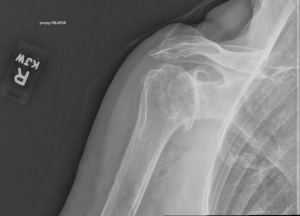

CASE 1

This is a 74-year-old male with history of prior failed cuff repair now with rotator cuff tear arthropathy. There is significant posterior wear of 18 degrees combined with 10 degrees of superior inclination. This is a common wear pattern in rotator cuff tear arthropathy. By planning the posterior superior augment preoperatively, I was able to move the center starting point slightly posterior and place it in 6 degrees of retroversion, allowing the cage to stay within the vault and ream almost no bone. The 10-degree superior portion of the augment fit almost perfectly. Without the preoperative planning and the GPS navigation it would have been easy to ream away significant bone anteriorly to attempt a correction of the version. There also would have been no way to determine how much retroversion I was leaving the implant in order to ream minimally.